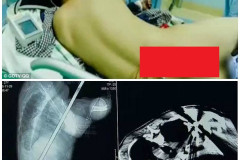

Все-таки ты, Кейт? Новые доказательства того, что Питт увлекся именно Хадсон Санта Димопулос поправилась к зиме, чтобы было теплее (Фото) Как безнадежная жертва анорексии смогла победить болезнь Голубая лагуна: стройный как кипарис Рики Мартин отдыхает на пляже с молодым воз... Новый тренд — красный макияж глаз. Советы стилистов (Фото) «Дикий Ангел», «Клон», «Санта-Барбара»: что стало с героями любимых сериалов СЕМИКЛАССНИЦА ИЗ КРАСНОДАРА МАРИЯ СВОИМИ ГОЛЫМИ ФОТО ШОКИРОВАЛА ОДНОКЛАССНИКОВ И... 12 самых добрых поступков 2016 года, из-за которых мы гордимся человечеством (Фото) Выбрались с женой в Париж... Больше мы такой ошибки никогда не допустим! Наталья Орейро едва не пострадала в давке в Санкт-Петербурге (Фото) Ленинаканский пробор: история парикмахерской, пережившей землетрясение в Гюмри Работа над ошибками природы: 10 российских звезд, сделавших пластику до 30 лет Строитель, насквозь проколотый громоотводом, остался жив Закройте глаза, ткните мышкой в таблицу и прочтите ваше новогоднее предсказание Царский подарок к новому году «Океаническая брюнетка» — самое модное окрашивание сезона (Фото) Эту задача по зубам лишь настоящим сыщикам. Посмотри на картинку и раскрой прест... Муж отключил умирающую жену от аппаратов, и тут она прошептала: «Я буду…» Горячие дамы на пляжах Бразилии (Фото) Неделю назад мне случилось удостоиться диплома лауреата Тысячи пользователей «Фейсбука» поддержали девушку, получившую слишком дешёвое о... Шуба и пикантный разрез до бедра: Ани Лорак поразила откровенным образом (Фото) 15 доказательств того, что умелый визажист может изменить внешность до неузнавае... Киркоров - большой поклонник женского секонд-хенда (Фото) Ольга Бузова: Тарасов приехал с друзьями-кавказцами и выкинул меня из квартиры (... Женщина, родившаяся без влагалища, прошла через хирургическую операцию, изменивш... Тройное чудо: крошечные тройняшки, родившиеся на 23-й неделе, выжили и попали в ... Купальник и сапоги: поклонники не оценили смелый образ солистки группы "А-Студио" Тест: Выберите дверь и узнайте , что ждет вас в ближайшем будущем. Как в воду гл... Дима Билан снимет клип к годовщине Геноцида армян